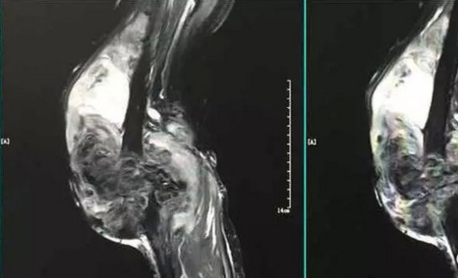

核心提示:色素沉着绒毛结节性滑膜炎是滑膜的一种增生性病变,经常表现为局限的结节。肿块可能起源于关节滑膜、腱鞘、筋膜层或韧带组织。病变表现为无痛性软组织肿块,通常位于手指和足趾处。色素沉着绒毛结节性滑膜炎的饮...

核心提示:膝关节骨性关节炎在我们生活当中是非常常见的一种疾病,很多中老年人都患有这种关节炎。如果得上这种关节炎的话,会给老人的生活起居带来非常大的不便,所以对膝关节骨性关节炎的治疗和饮食调节都非常重要。  膝...